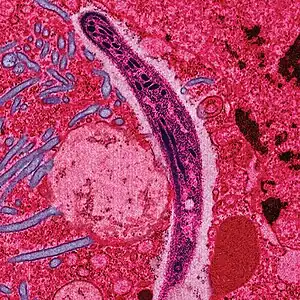

![]() | |

| False-color electron micrograph of a Plasmodium sporozoite | |